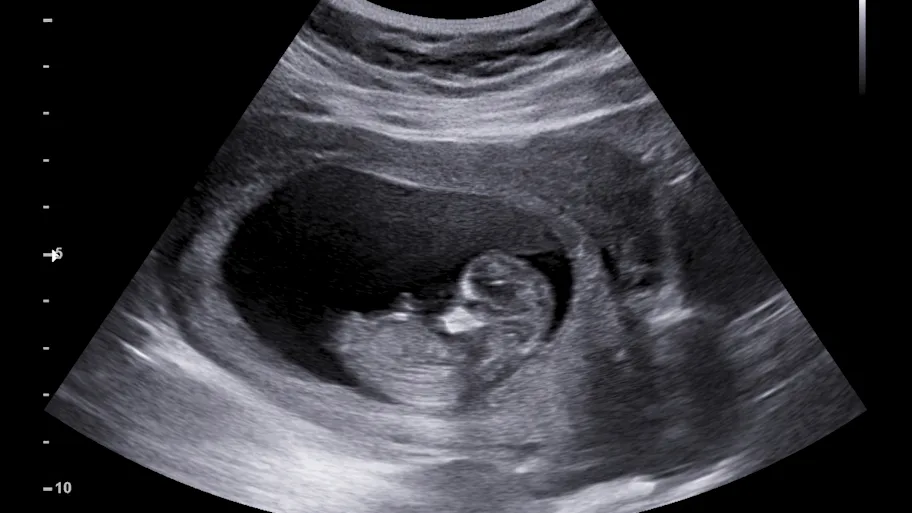

Precarious housing, financial hardship, and disadvantages based on ethnicity are just some of the factors that can result in negative pregnancy outcomes. They are also the reality that many women in one of the UK’s most diverse and deprived cities find themselves in. Researchers in Birmingham have examined how demographics, deprivation, and lifestyle factors impact the odds of babies being born too early or too small, as well as the odds of neonatal mortality. They estimated that if all women had the same odds of adverse pregnancy outcomes as White women living in less deprived areas, 211 low-weight and 191 premature births could be prevented each year in Birmingham and Solihull.

In Birmingham, 43% of the population live in the most deprived 10% of neighborhoods in England. It is well known that deprivation can lead to adverse pregnancy outcomes, including low birth weight, premature birth, stillbirths, and neonatal mortality.

Now, researchers there examined the association between demographic, socioeconomic, and lifestyle factors and the risk of adverse birth outcomes in Birmingham and neighboring Solihull, an area much less affected by deprivation.